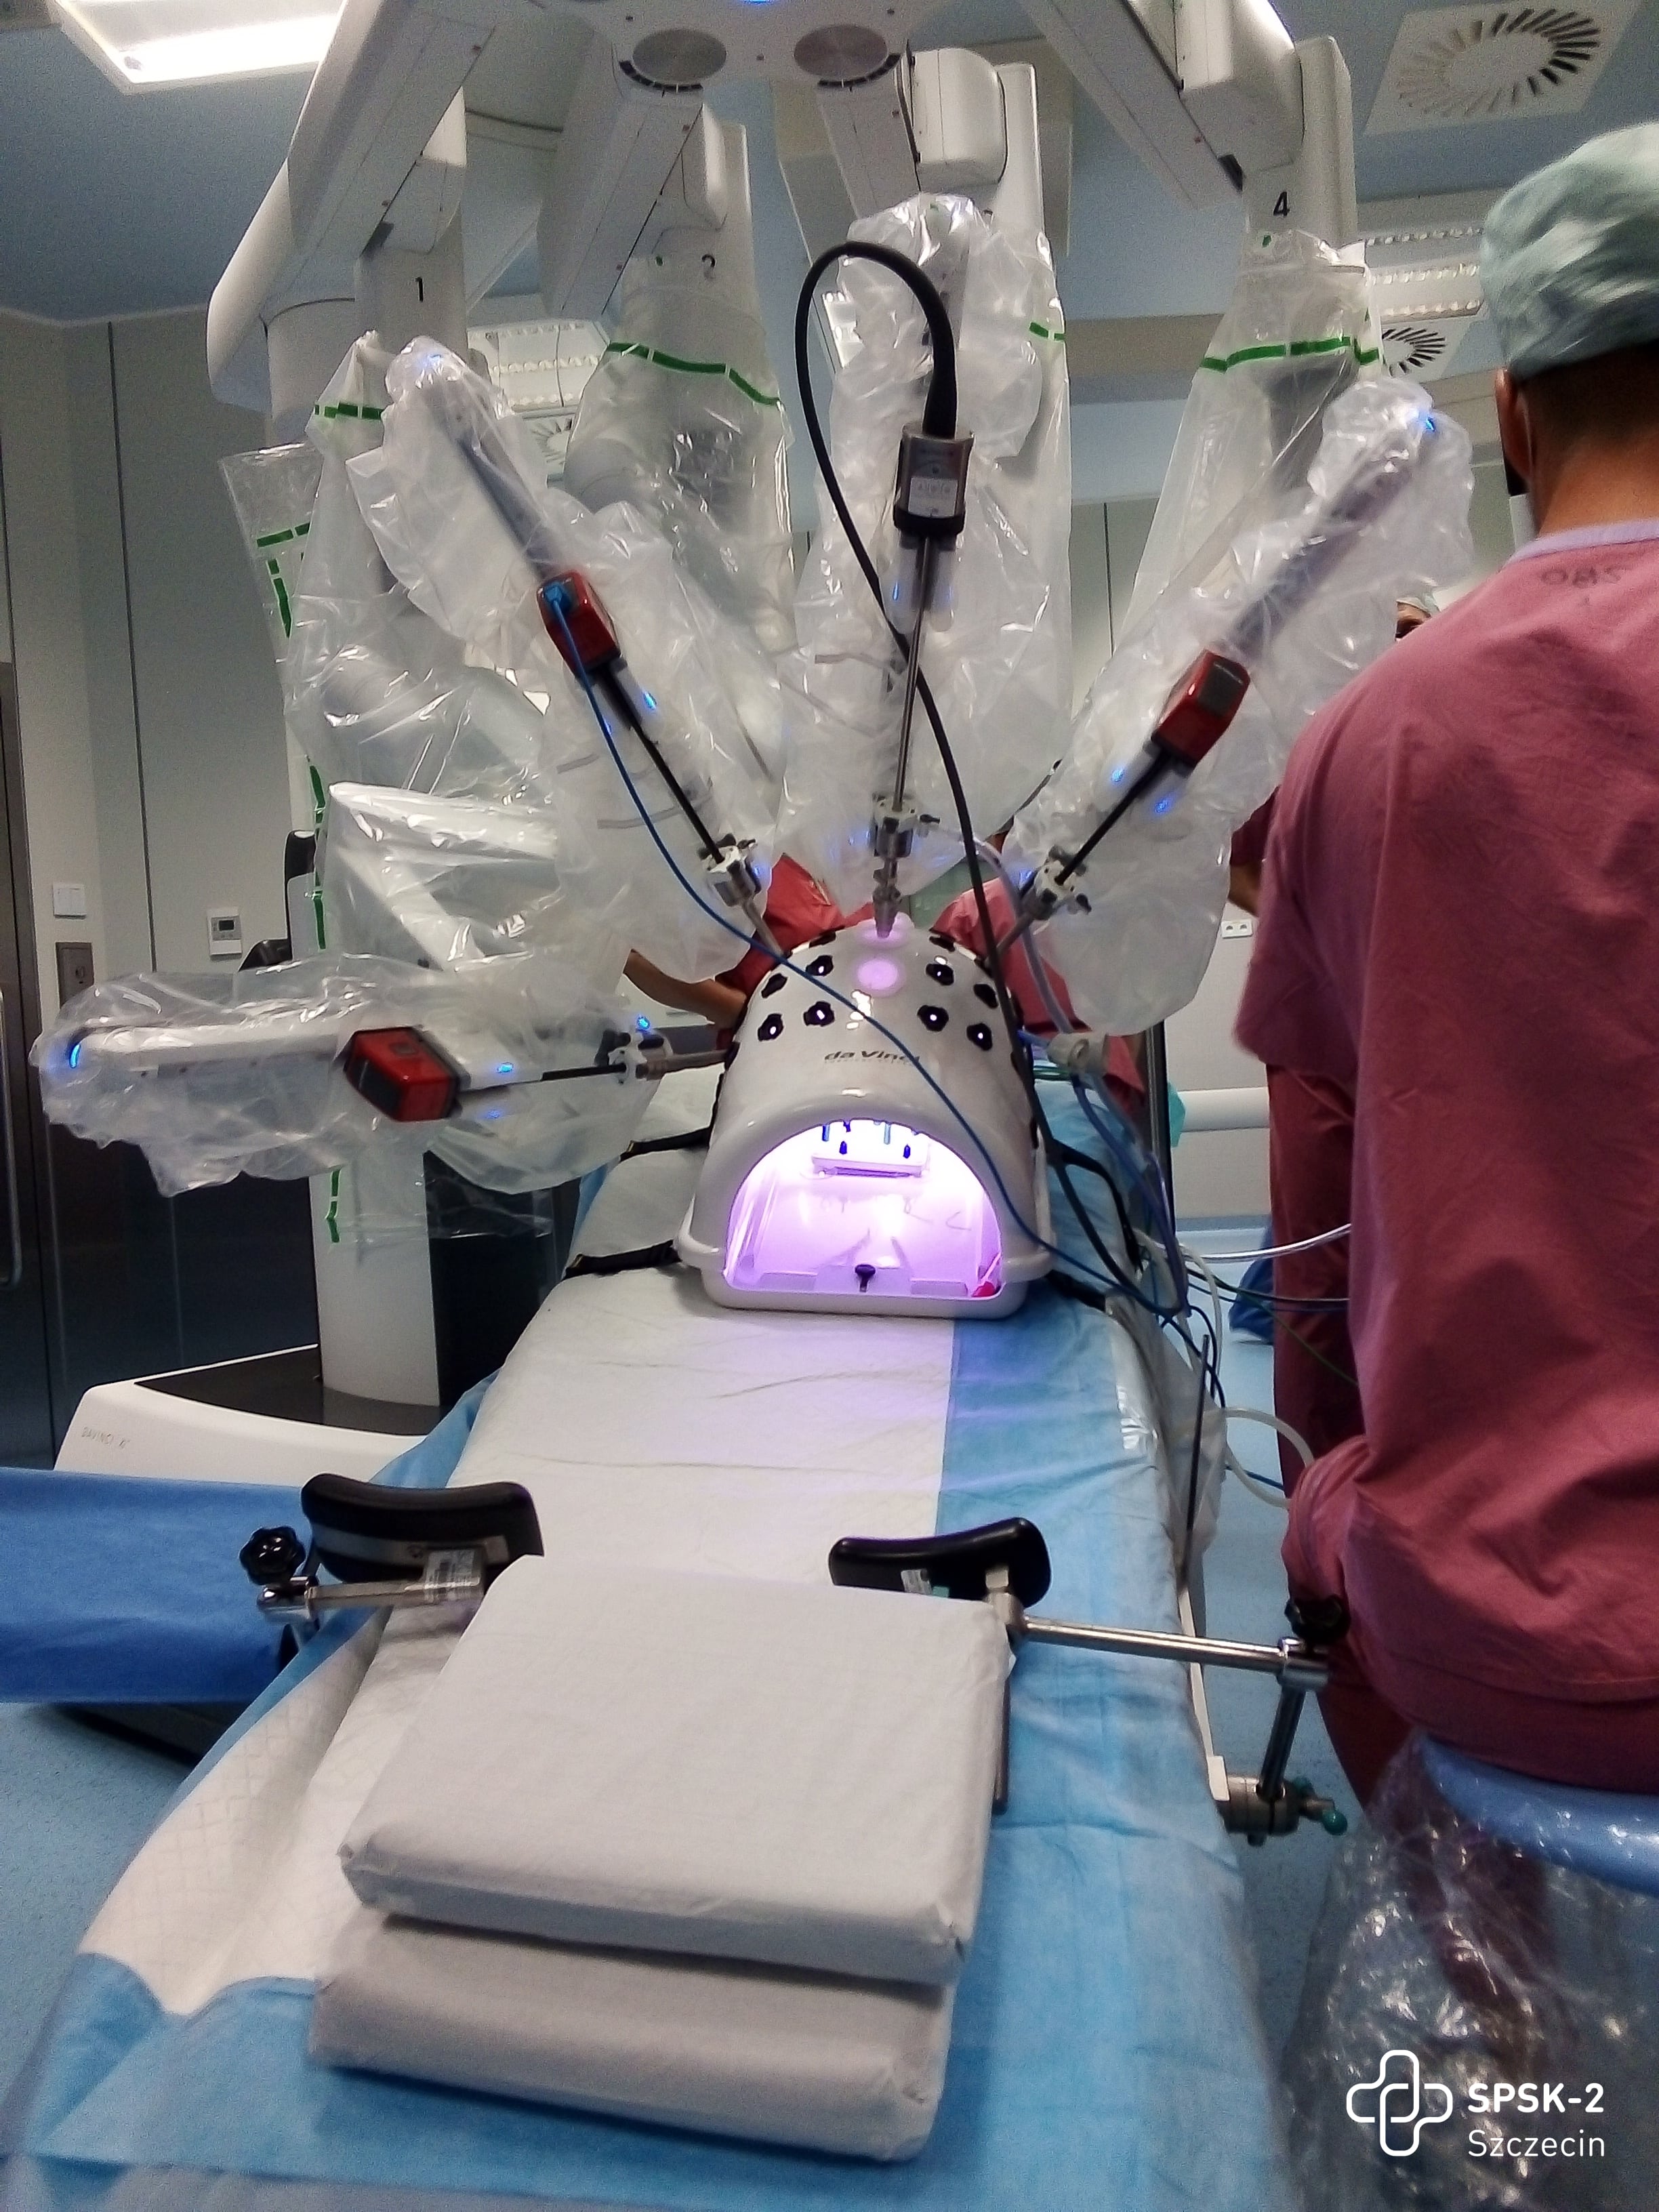

Fundusze przyznane dla naszego szpitala pozwolą podwyższyć poziom opieki onkologicznej naszych pacjentów. W ramach przyznanej kwoty planujemy m.in. zakup drugiego systemu chirurgii robotycznej, co pozwoli na podwojenie liczby operacji małoinwazyjnych. Nowością będą dwie konsole operacyjne, umożliwiające współpracę dwóch chirurgów w trakcie zabiegu. Szpital wzbogaci się również o aparaty RTG i USG, laser medyczny, robot cytostatyków, który trafi do szpitalnej apteki, ponad 100 łóżek szpitalnych, system mikroskopii wirtualnej, siedem stołów operacyjnych oraz dwa zestawy laparoskopowe. Na liście zakupowej znajduje się blisko 130 pozycji, obejmujących blisko 400 urządzeń, co znacząco poprawi jakość świadczonych usług i komfort pacjentów.

Wywiad z prof. Marcinem Słojewskim, lekarzem kierującym Kliniką Urologii I Onkologii Urologicznej USK-2 w Szczecinie na temat systemu robotycznego da Vinci

2023-12-28Link do wywiadu: www.facebook.com/TVPSzczecin

12.10-12.30 Operacje przy wsparciu systemu robotycznego da Vinci

12.10-12.30 Operacje przy wsparciu systemu robotycznego da Vinci